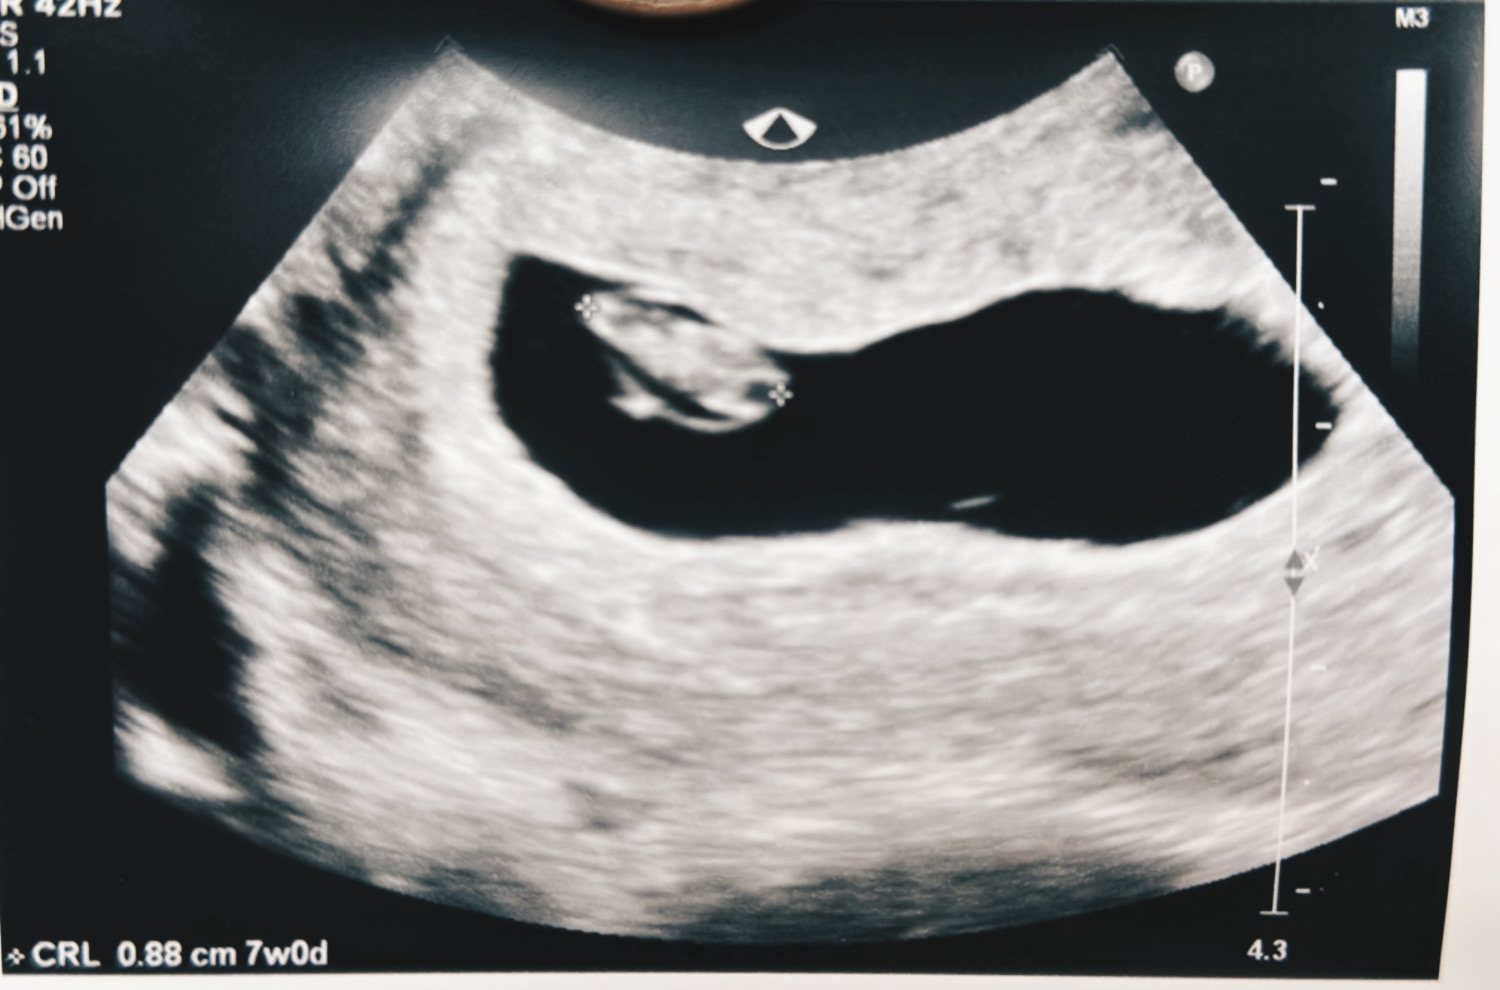

10/14(5W6D) 陰道超音波照到胚囊和胚胎,並偵測到心跳 。(胚胎大小2.42mm)

10/7(4W6D) 陰道超音波照到胚囊大小約3.89mm